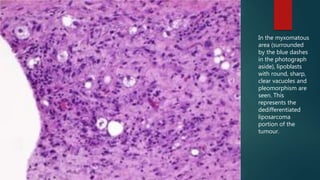

In the myxomatous

area (surrounded

by the blue dashes

in the photograph

aside), lipoblasts

with round, sharp,

clear vacuoles and

pleomorphism are

seen. This

represents the

dedifferentiated

liposarcoma

portion of the

tumour.

In the myxomatous area(surrounded by the blue dashes in the photograph aside), lipoblasts with round, sharp, clear vacuoles and pleomorphism are seen. This represents the dedifferentiated liposarcoma portion of the tumour.